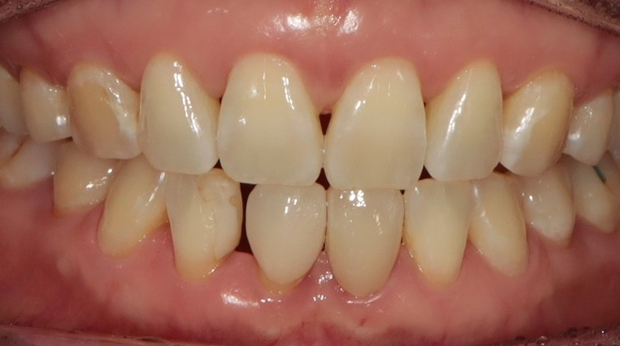

라미네이트